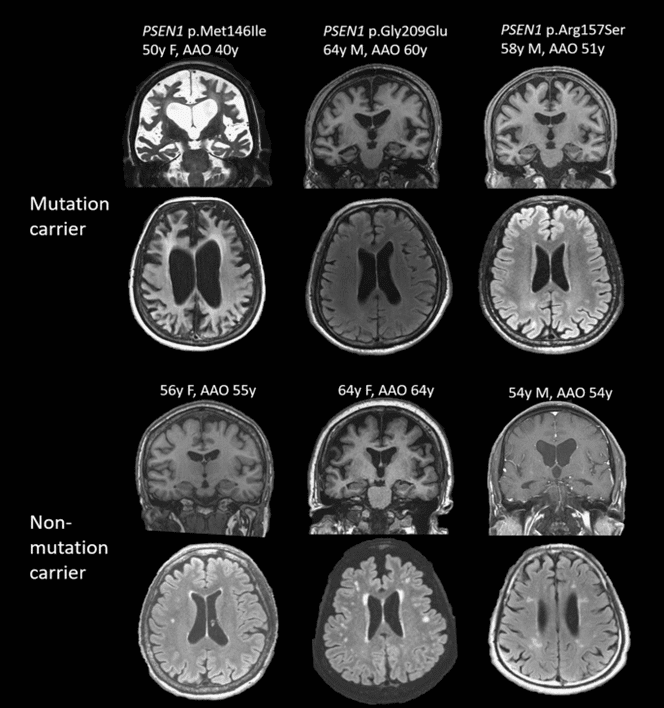

Brain atrophy in women and men with amnestic mild cognitive impairment

Men and women with Alzheimer disease experience different cognitive and psychiatric symptoms. Women undergo faster cognitive decline after diagnoses with mild cognitive impairment or dementia.

Brain atrophy rates and patterns differ between genders along the disease continuum; in mild cognitive impairment, brain atrophy is more rapid in women than in men.

MRI of 3 mutation carriers and non-carriers with a predominant mutation PSEN1 p. Met146Ile.

13% of familial early onset Alzheimer disease instances are autosomal dominant, affecting at least three generations. Most Alzheimer’s cases tend to be complicated, involving numerous susceptibility genes and environmental variables.